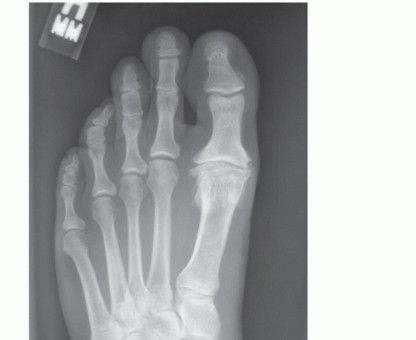

SURGICAL MANAGEMENT The primary indication for a chevron osteotomy is symptomatic hallux valgus deformity wit…

DEFINITION Paul W. Lapidus originally described a procedure for the correction of hallux valgus in 1934. This…

BACKGROUND The proximal opening wedge osteotomy is one of the more than 150 procedures described for the trea…